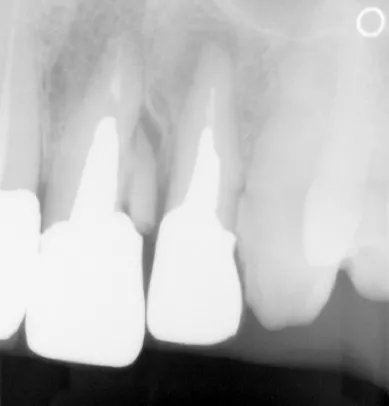

レントゲン撮影を行ったところ、左上前歯(中切歯/1番)の歯の根が破折しており、治療して残すことは難しく抜歯が必要な状態でした。

また、破折した前歯とその両隣の歯(右上中切歯、左上側切歯/2番)は被せ物で治療されていましたが、色が劣化していて気になるとのことでした。